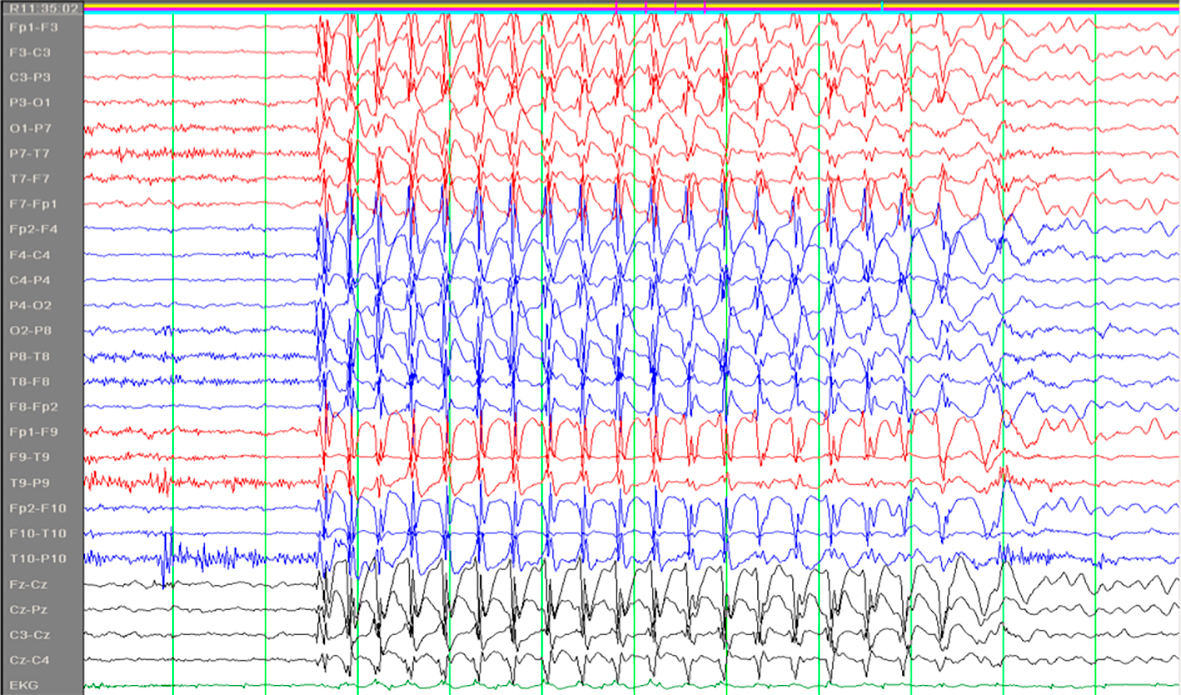

Absenser er en type epileptiske anfall som kan ses ved flere generaliserte epilepsiformer, først og fremst ved absensepilepsi i barnealderen. Ordet stammer fra det franske absence og det latinske absentia og kan oversettes med åndsfravær. Barna blir i noen sekunder fraværende i sin virksomhet eller tale, uten at vedkommende selv merker det. De får et tomt, stirrende blikk. Det er ingen kramper, men av og til ses diskrete rykninger i øyelokkene. Det er viktig at foreldre er oppmerksomme på slike tilfeller hos barn. Absensene har et spesifikt EEG-korrelat; 3/sekund «spike-waves» (fig 1) (1).